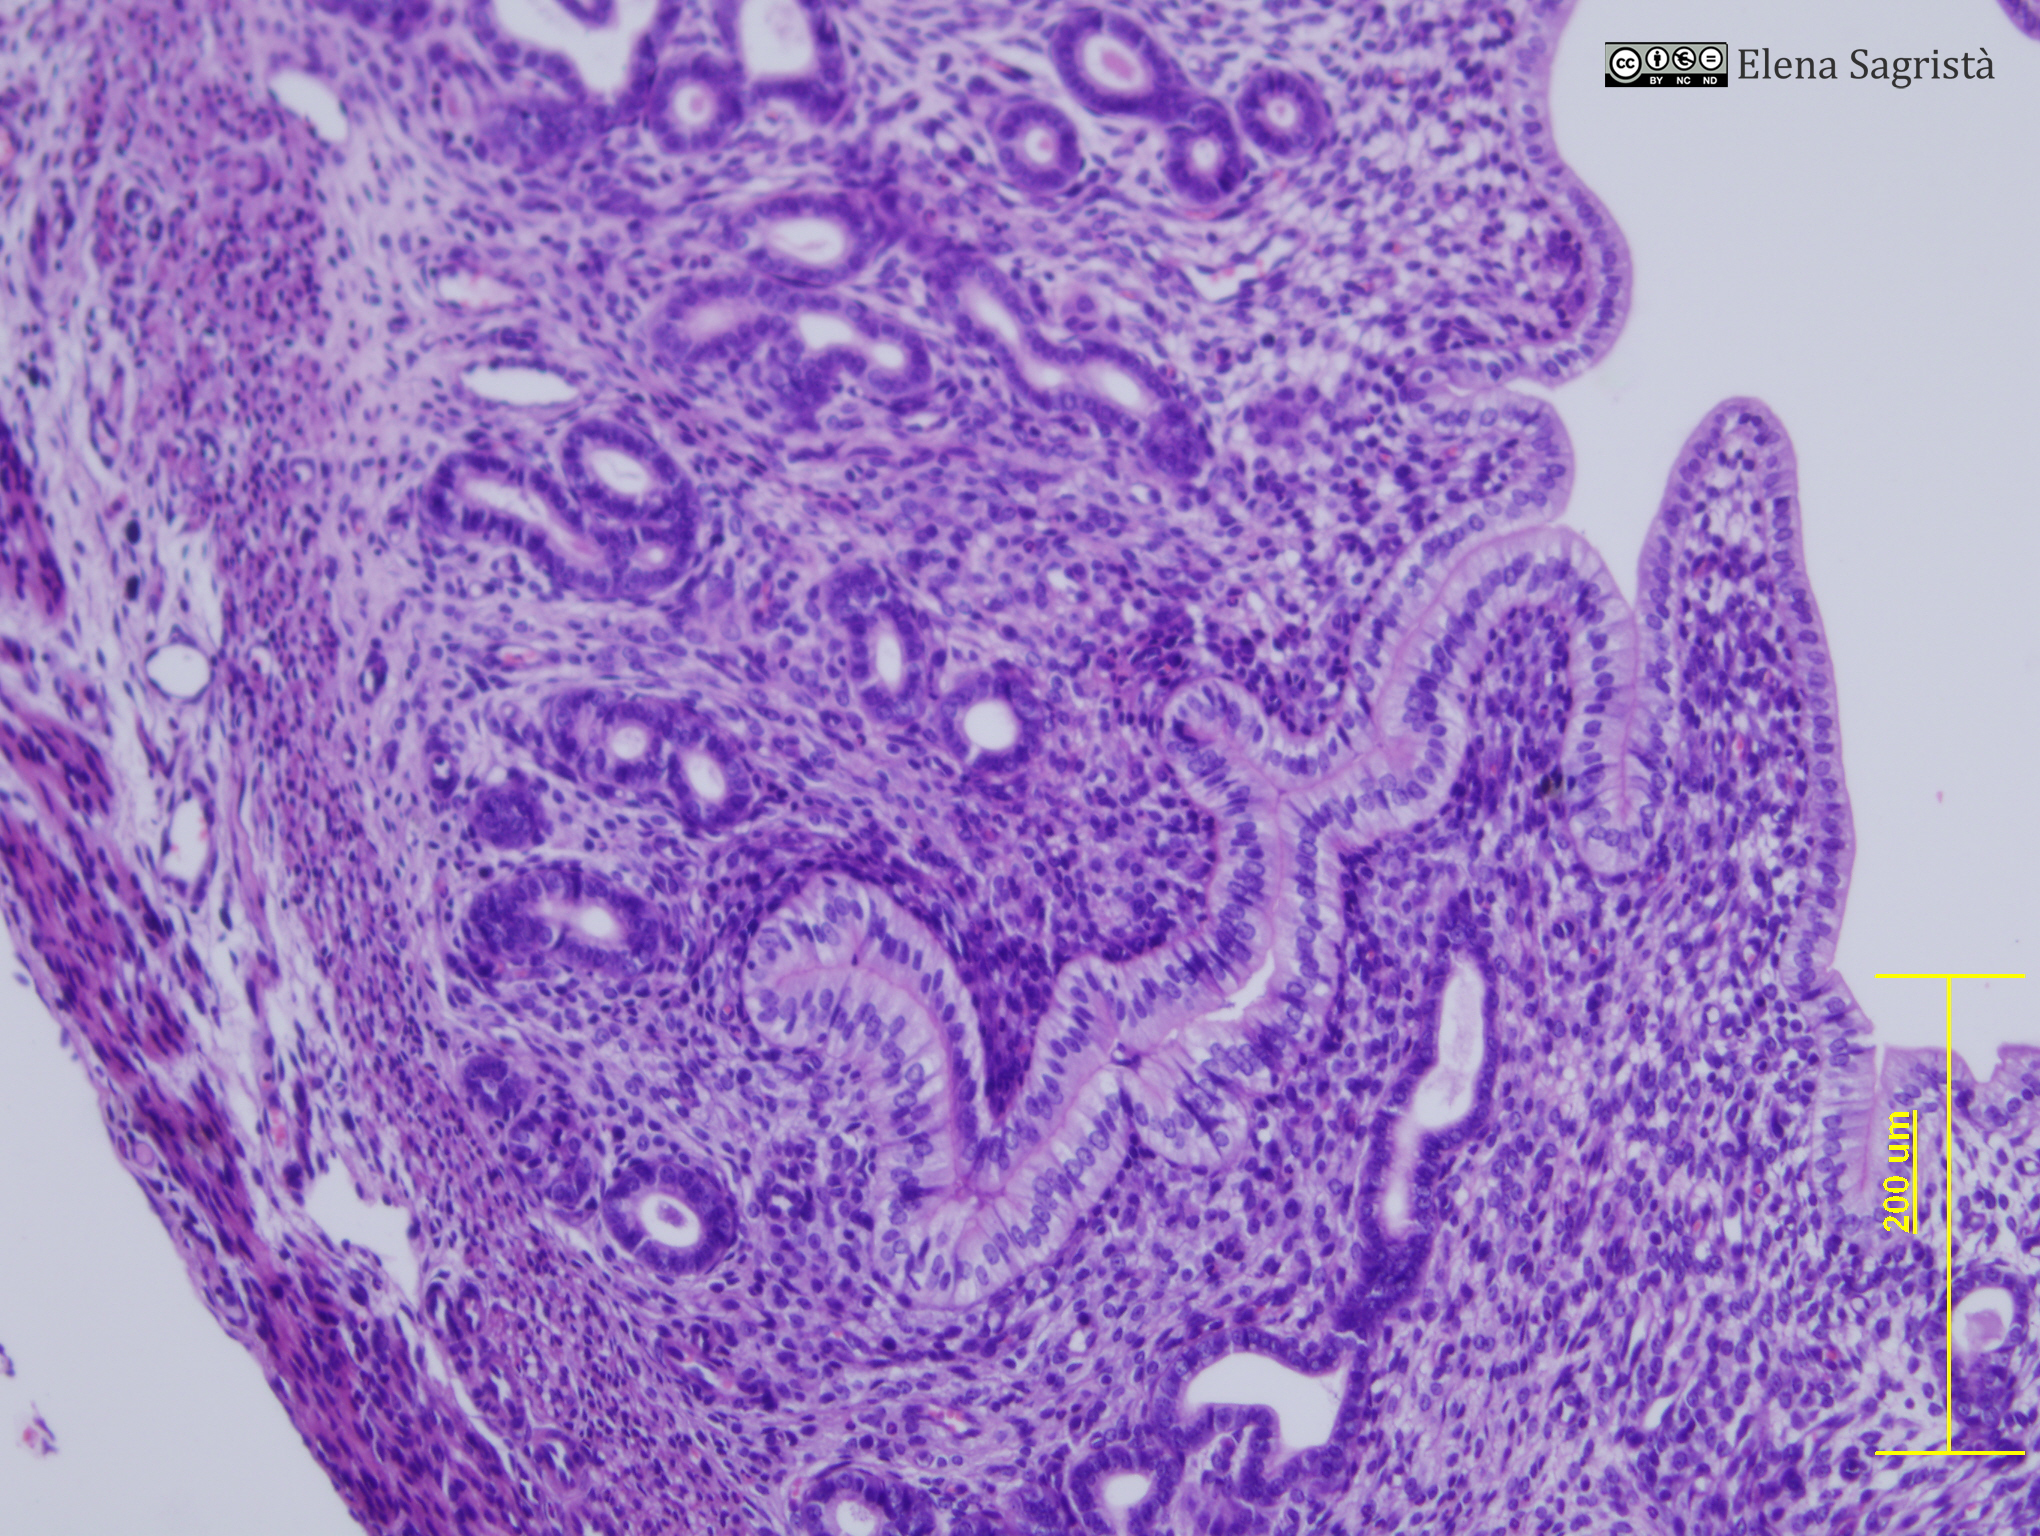

Histologia imatges: 23 Ovari i Aparell reproductor femení

Imatges de preparacions histològiques d'Ovari i Aparell reproductor femení. Microscòpia òptica.